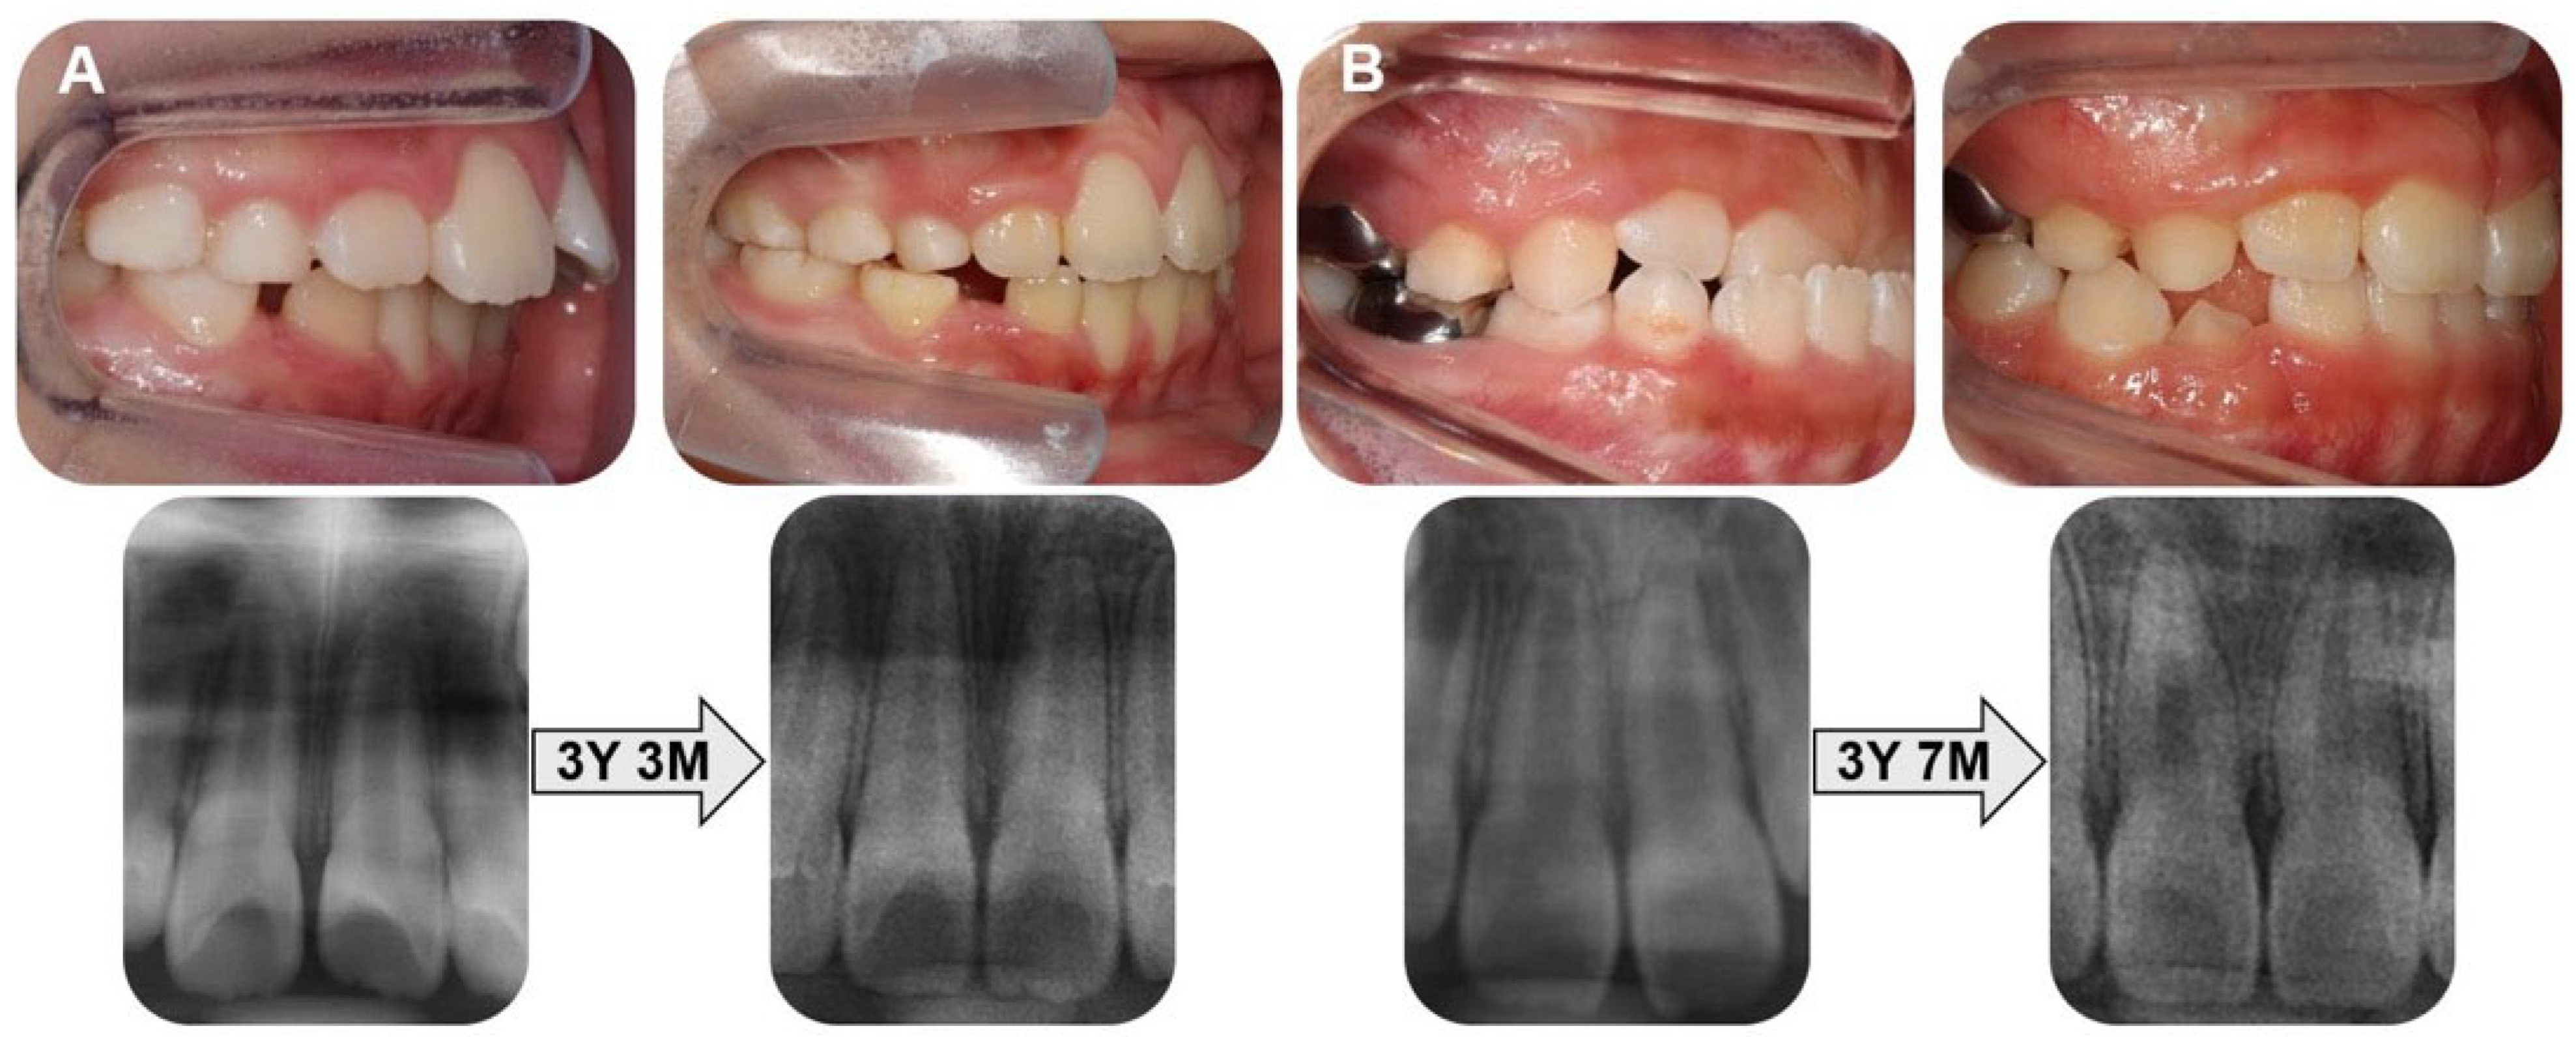

2.4. Study Methods